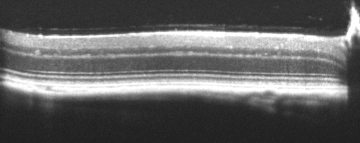

Retina

Bioptigen sdOCT Retinal Image